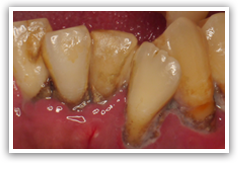

なんだこれは!と思われるかもしれませんが、これは重度の歯周病にかかった患者さんの口の中の写真です。上の歯はほとんど抜け落ち、残っている下の歯も歯石まみれでグラグラです。忙しかったり、痛みがなかったのでまあいいかと20年来歯医者にいかないまま放っておいたら、前歯が抜けてしまって見た目がかっこ悪いということで来院されました。

下の前歯の裏側を鏡で見てください。普段歯医者に行かない方には歯の根元に写真のような白い塊が付いている可能性が高いです。これは歯石と呼ばれ歯の汚れ(歯垢、プラーク)が固まって(石灰化)しまったものです。この歯石自体には病原性は無いとされていますが、その表面は歯と比べるとザラザラで、歯石の周りには新たな汚れ(歯垢、プラーク)が付着しやすくなっています。